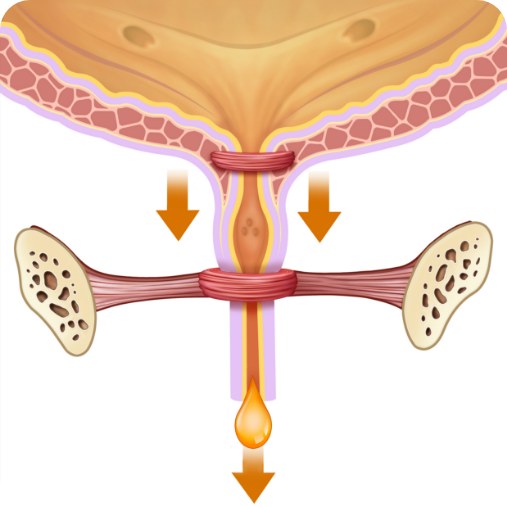

PRIMA del trattamento:

Muscoli deboli dell'uretra

DOPO il trattamento:

Muscoli forti dell'uretra